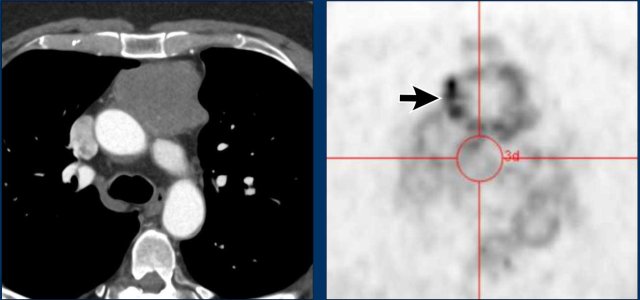

These images are of a 34-year-old female with dyspnoe.

Study the images.

What is your opinion?

Images

There is a cystic mass in the prevascular mediastinal space.

There are thick enhancing walls.

Because it still wasn't clear what we were dealing with a PET was performed.

Continue with the PET images...

Based on the PET-findings which diagnosis is the most likely?

Is it a cystic thymoma, complicated cyst, neuroendocrine tumor or a lymphoma?

The PET shows multiple lesions, which must be pathologic lymph nodes.

Discussion

A thymoma is almost never accompanied by lymphadenopathy.

An infected cyst could also give rise to lymphadenopathy, but not so widespread as in this case.

Final diagnosis

Cystic lymphoma.